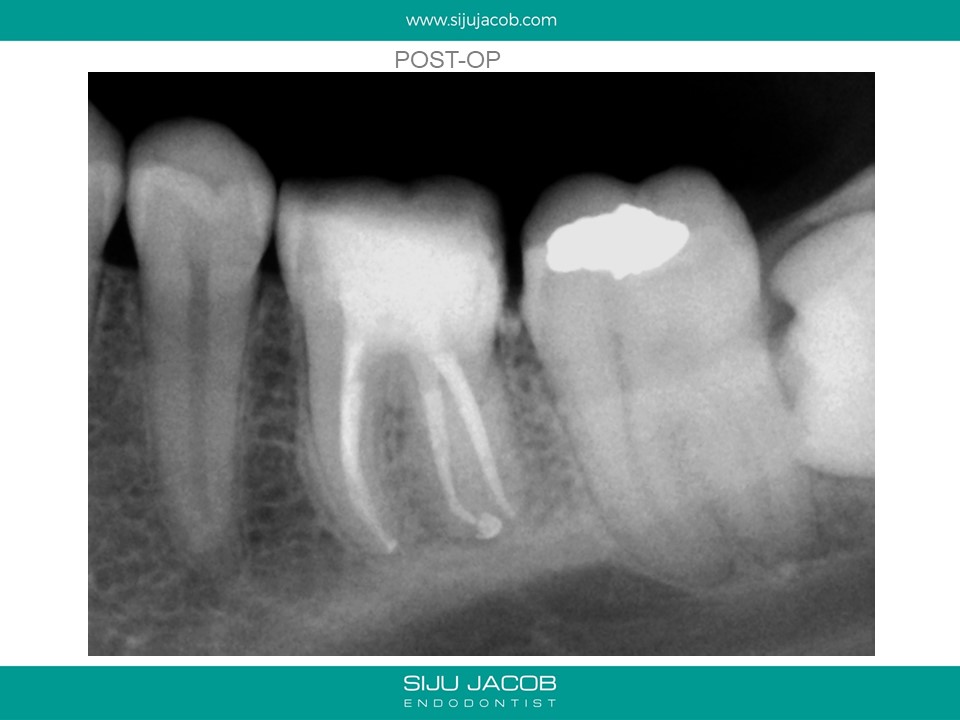

This patient had sensitivity to cold after an RCT on a lower molar. Sensitivity persisted even after a month. Re-treatment revealed a missed distal canal/root that was still vital and hyperaemic.